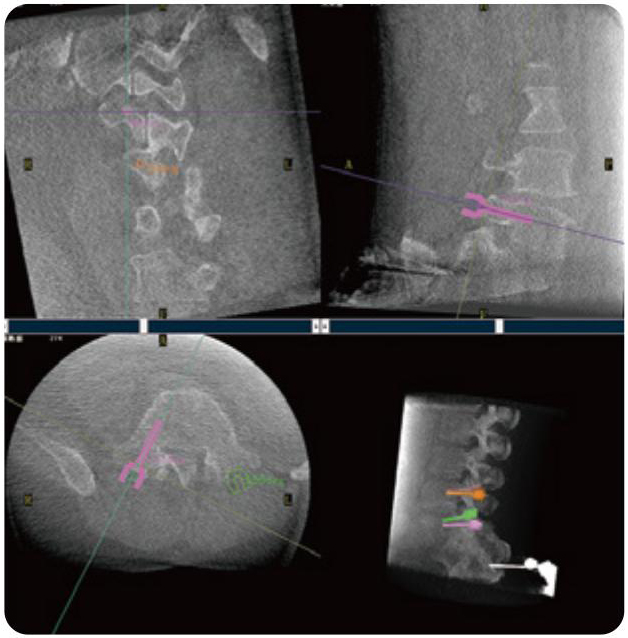

PL300B可應(yīng)用于多節(jié)段脊柱外科手術(shù),輔助醫(yī)生定位病灶部位,為脊柱外科手術(shù)(經(jīng)皮椎體成形術(shù)、椎弓根螺釘內(nèi)固定術(shù)等術(shù)式)提供術(shù)前手術(shù)流程規(guī)劃、入釘位置、角度可視化引導(dǎo),模擬仿真入釘輔助。

PL300B搭配普愛醫(yī)療自主研發(fā)生產(chǎn)的平板3D C形臂,借助一體化自適應(yīng)配準( 軌跡配準)技術(shù),通過追蹤C形臂三維采集軌跡,自動完成圖像坐標建立和系統(tǒng)坐標配準。配準精度更高,操作步驟少,系統(tǒng)運作效率高。